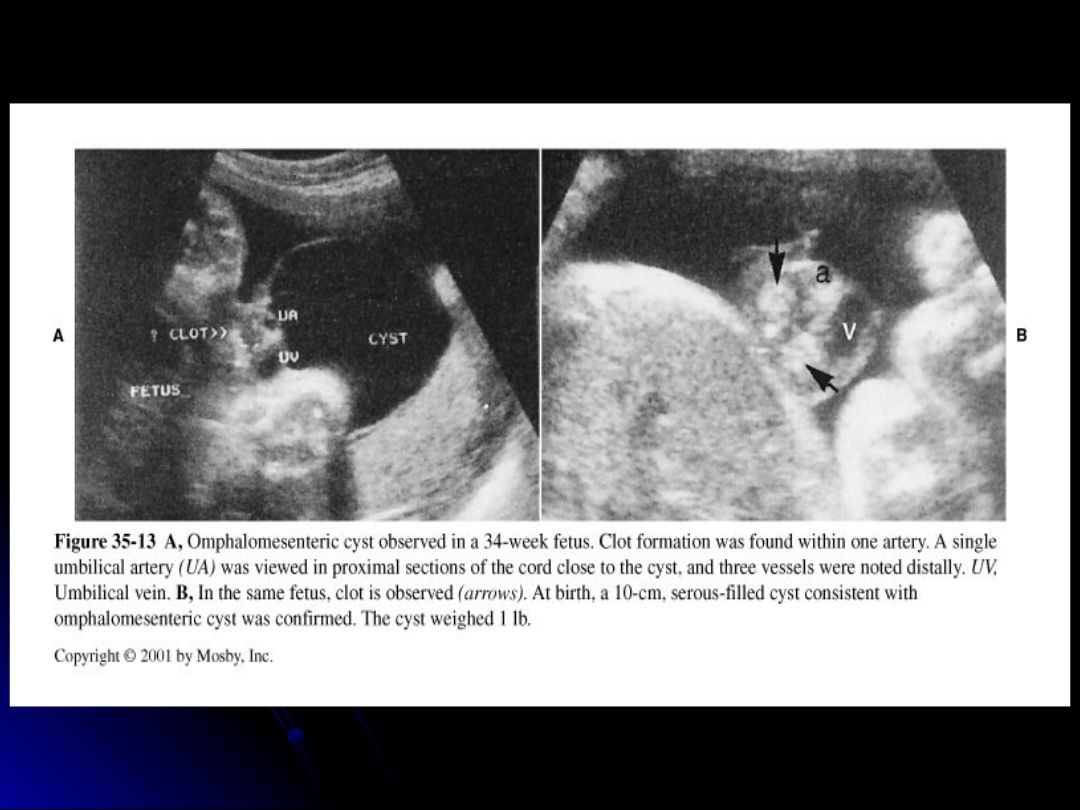

Which of the following statements about omphalomesenteric cysts is/are correct?

They are caused by persistence and dilation of a segment of the omphalomesenteric duct.

They may be up to 6 cm in size.